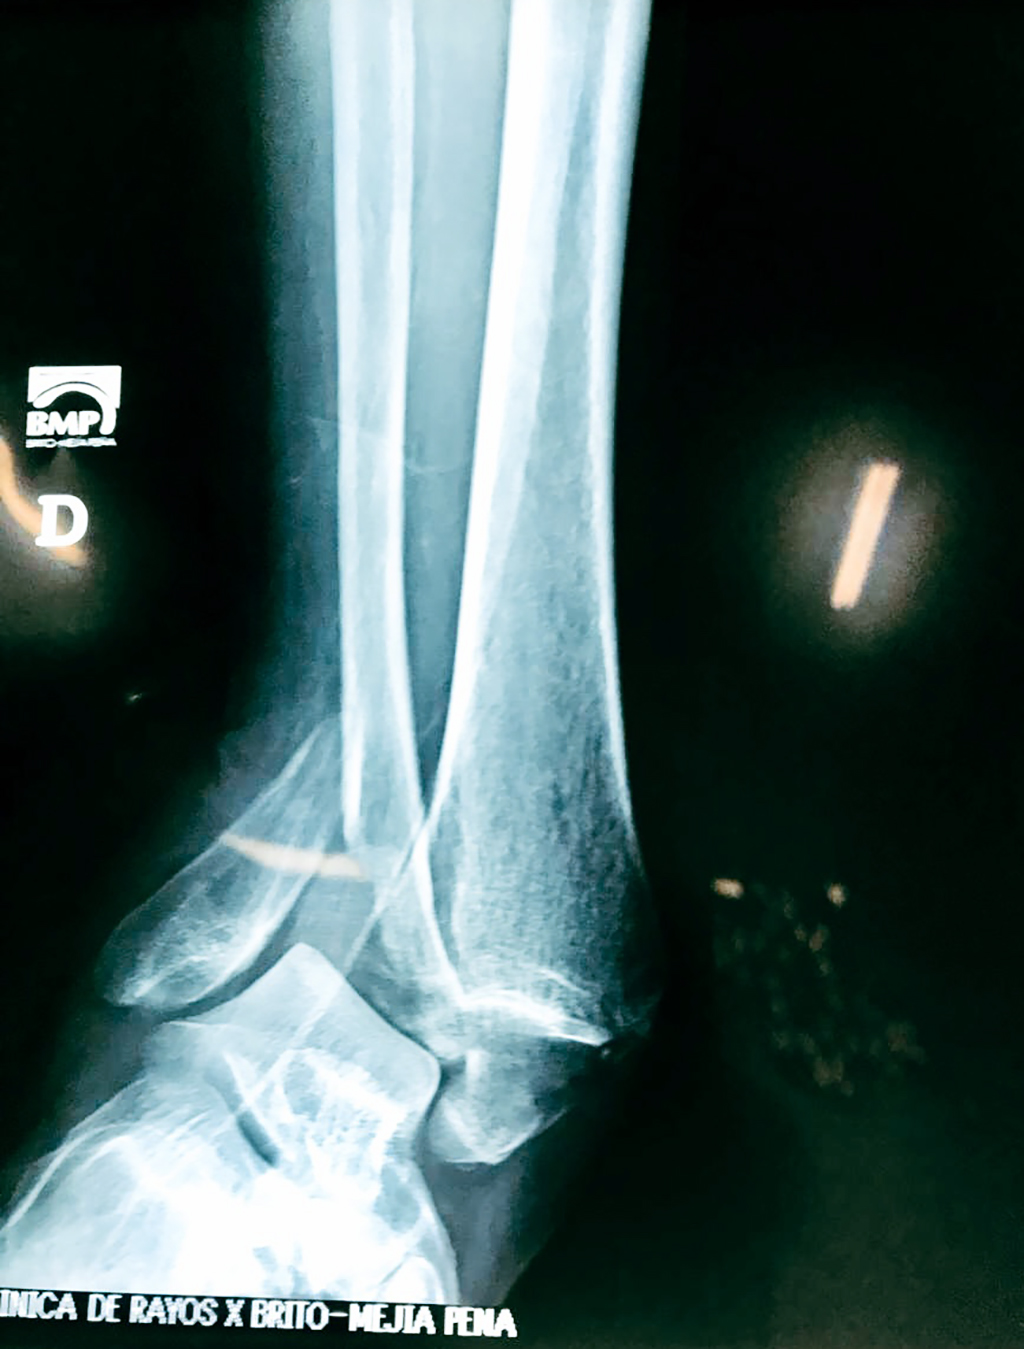

Una fractura de tobillo es la rotura de uno o más de los huesos del tobillo. Estas fracturas pueden ser:

- Parciales (el hueso está sólo parcialmente fisurado, no del todo).

- Completas (el hueso está perforado y está en 2 partes).

- Los extremos de los huesos están desalineados entre sí (desplazados).

- La fractura se extiende hasta la articulación del tobillo (fractura intra-articular).

- Los tendones o ligamentos (tejidos que sujetan los músculos y los huesos entre sí) están rotos.